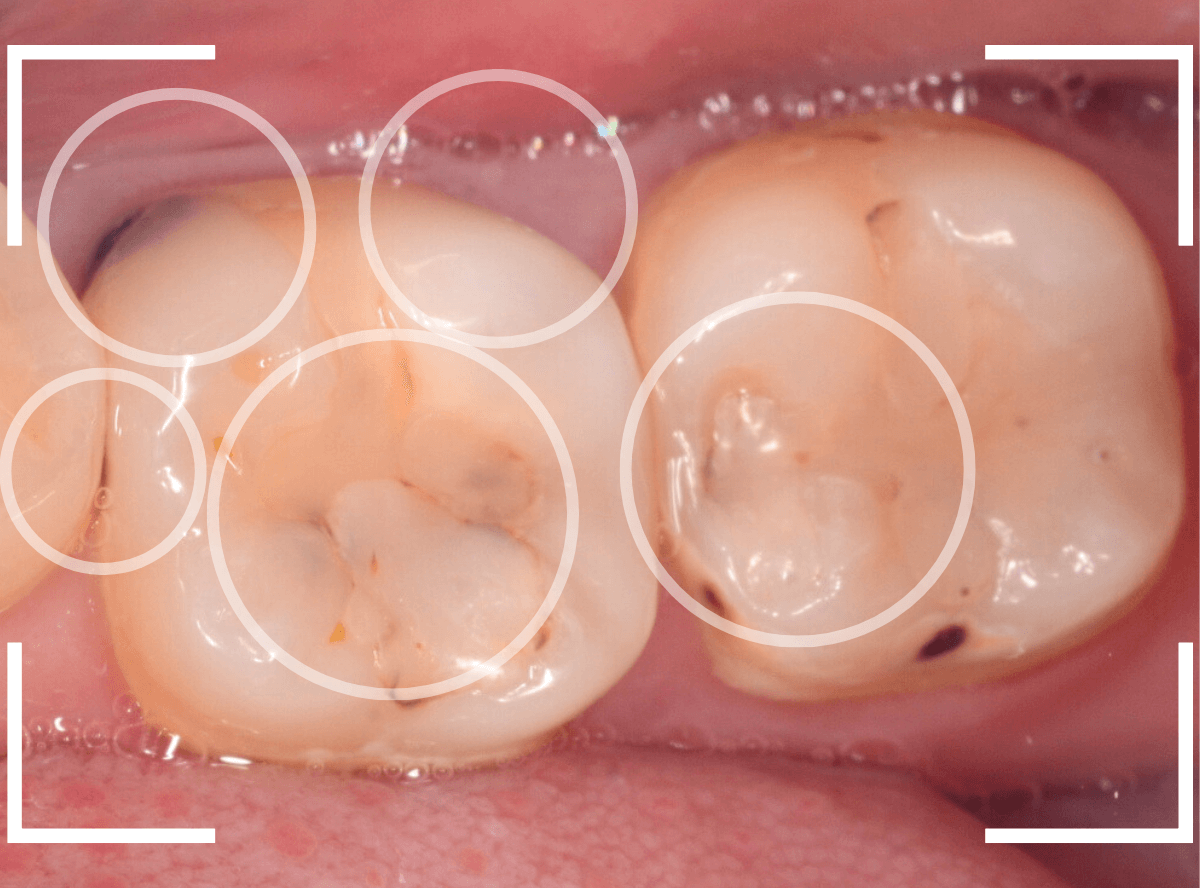

Case.8 大きな虫歯なのに、レントゲンではっきり写らない

こちらも定期検診希望で来院された患者さんです。

お口の中を拝見すると、明らかに虫歯がありました。

3本虫歯になっており、特に中央の小臼歯はかなり大きな虫歯になっているのが予想されます。

治療前にレントゲン写真で虫歯の大きさを確認するつもりが・・・あまりはっきり写ってきません。

患者さんに状況を説明して、歯を少しずつ削りながら虫歯を確認する事になりました。

このように明らかに大きな虫歯があると診断されるような状況でも、レントゲン写真でうまく診断できない場合もあります。